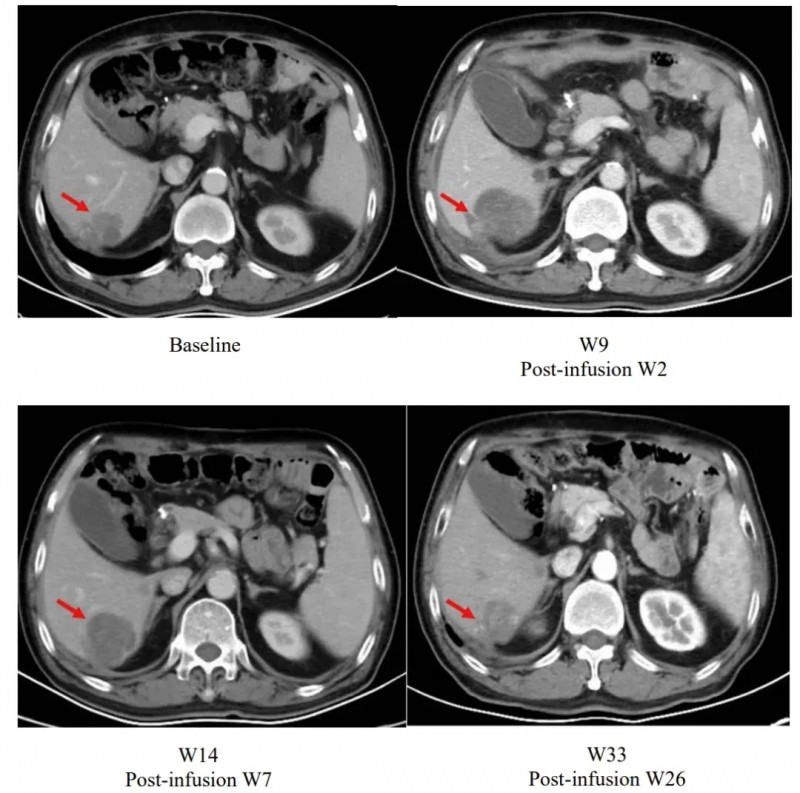

其中一个合并肝转移的胃癌患者治疗效果尤为突出。该患者在输注satri-cel后第2周,肝脏上的病变比基线大。但在后续随访观察中,病灶逐渐缩小,至输液后第26周时已小于基线水平(详见下图)。

▲图源“The Lancet”,版权归原作者所有,如无意中侵犯了知识产权,请联系我们删除